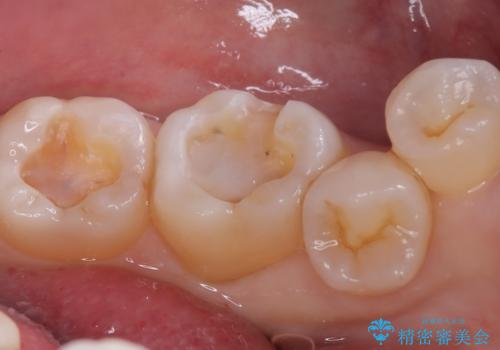

下顎大臼歯部に入っている保険適用のメタルインレーを、適合性と審美性の良いセラミックインレーでのやり替えとなりました。

メタルインレーを除去した際、古い裏層材やカリエスは除去し新たにCR裏層しています。